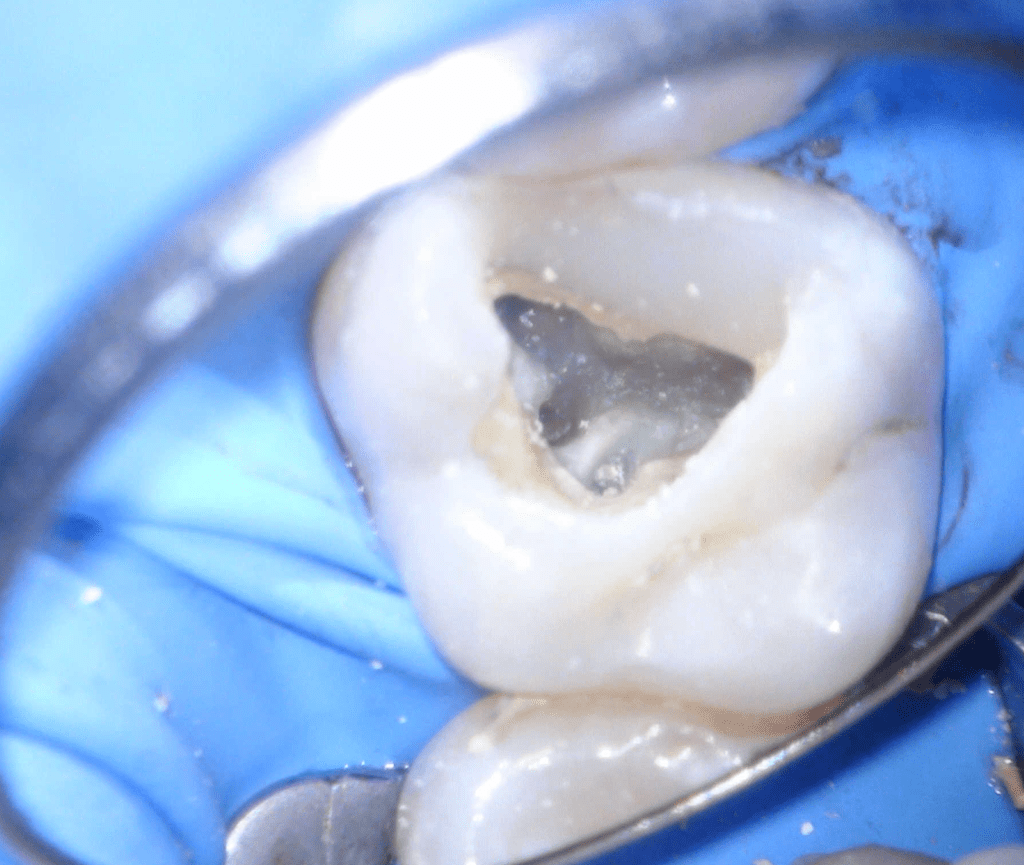

Fisura, remoción amalgama para explorar